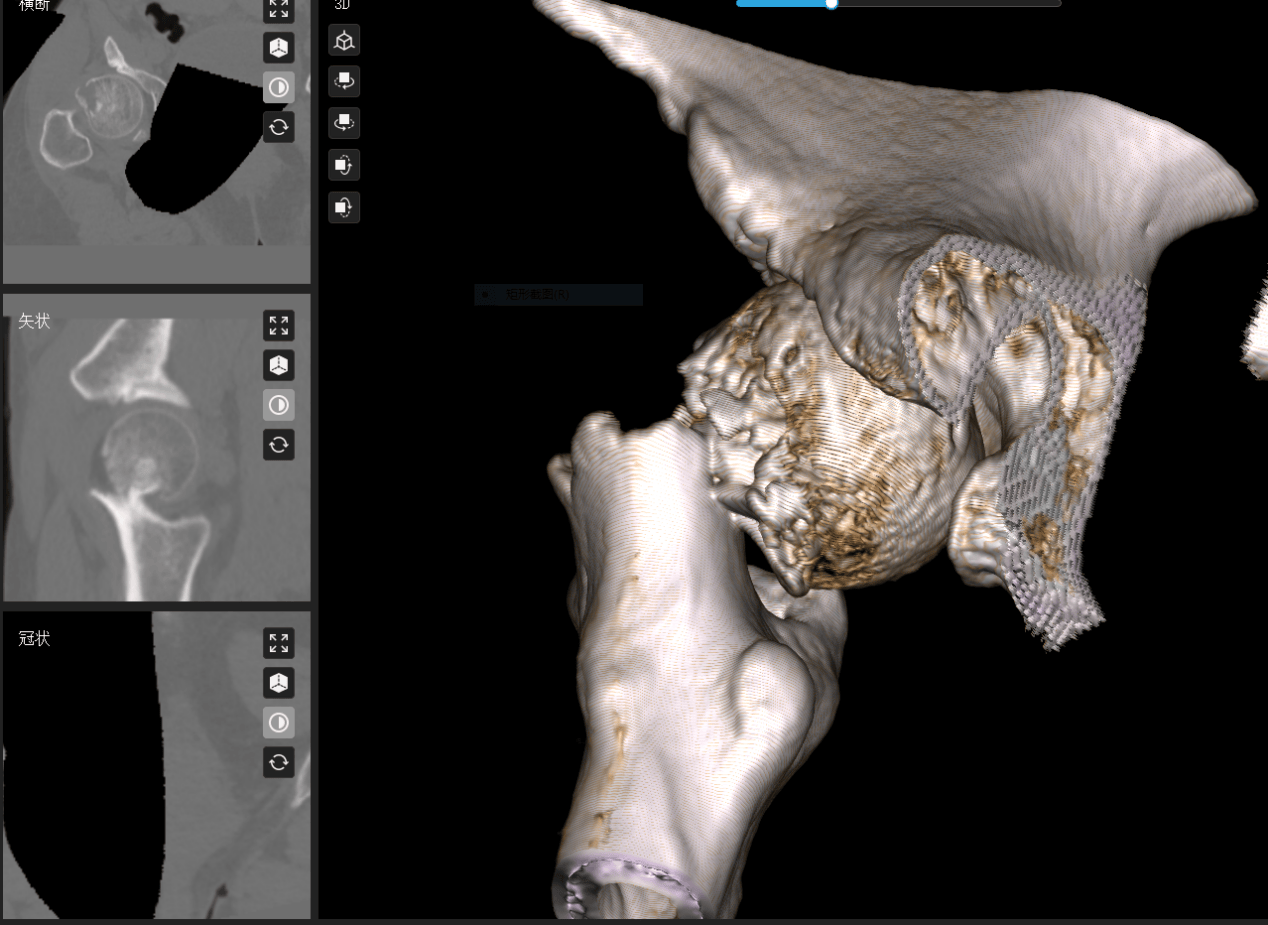

诊断结果冰冷而严峻:左侧股骨颈头下型骨折(Garden IV型),严重错位分离。这意味着高达40%以上的股骨头坏死风险,以及漫长的康复之路。

面对如此高风险、高难度的骨折(Garden IV型,严重错位),湖州邦尔骨科医院叶博士团队深知,传统的治疗方式难以满足患者快速康复、最大限度保髋的期望。他们迅速制定了以“Garden指数”为金标、数字化微创技术为核心的精准治疗方案。

2. 机器人赋能微创固定: 利用先进的骨科机器人及数字化导航技术,叶博士团队实施了空心螺钉内固定术。

技术亮点:

亚毫米级精度(0.8mm): 将螺钉置入精度提升至亚毫米级,显著优于传统手法 ;

最大化保护血供:精准避让脆弱血管,最大限度保护股骨头残存血供,这是降低坏死风险的关键。

3. 动态监测护航: 术后康复并非终点。团队全程动态监测Garden指数,确保其稳定在安全解剖范围内。术后6周结合MRI(如T2WI信号)科学评估股骨头血供变化,为康复计划提供精准依据。

4. 研究证实,复位偏差>2mm会使坏死风险骤增,而精准复位使其归入低风险。